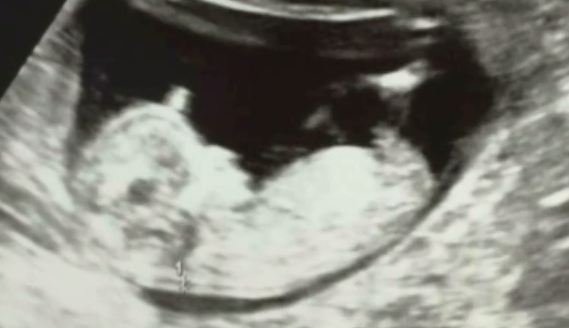

Momentan nu stie ce o sa fie, insa vedeta KanalD isi doreste ca micutul pe care-l poarta in pantace sa fie baiat. Ilinca Vandici a facut publica prima ecografie cu bebelul.

„Eu imi doresc sa fie baiat, dar nu stiu. Sunt insarcinata in 12 saptamani. Sunt foarte fericita, incantata si emotionata.